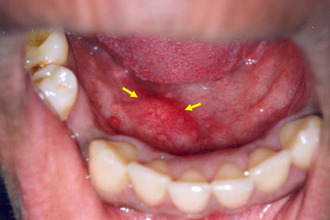

Если миндалина значительно увеличена, ее можно заметить, хотя в норме она не видна.

Для осмотра ротовой полости проводятся фарингоскопия и ларингоскопия. Эти процедуры позволяют определить степень увеличения лимфоидной ткани и оценить состояние миндалин. Особое внимание уделяется языку, особенно его корню, где расположена миндалина.

- Воспалительных процессов в области корня языка, которые могут проявляться абсцессом, флегмоной или развиваться на фоне туберкулеза, сифилиса или кандидоза. При осмотре могут быть обнаружены пленки с плотной текстурой. Для уточнения диагноза проводится бактериологическое исследование.

- Кистозных образований в ротовой полости, имеющих четкие контуры, гладкую поверхность и упругую консистенцию.

- Доброкачественных опухолей (аденом), которые отличаются плотной структурой и гладкой поверхностью.

- Злокачественных новообразований, распознаваемых по бугристой поверхности, каменистой плотности и увеличению регионарных лимфоузлов. В этом случае для диагностики используется биопсия.